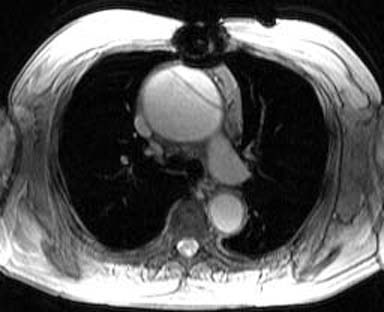

7) This spin echo image shows what aortic abnormality?